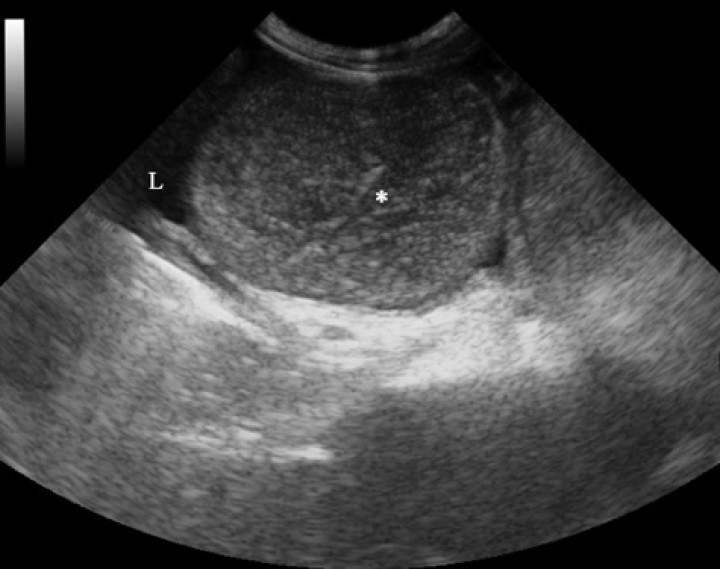

Por otra parte, la ecografía nos puede aportar información sobre la motilidad intestinal, la presencia de perforación y una peritonitis,[ Brown DC. Small Intestine. En: Tobias KM, Johnston SA (eds). Veterinary Surgery Small Animal. St Louis, Elsevier; 2012. 1513-1541. , Riedesel EA. Small bowel. En: Thrall DE (ed). Textbook of veterinary diagnostic radiology. Seventh edition. St Louis, Elsevier; 2018. 926-954. ] aunque la observación de un cuerpo extraño se ve dificultada cuando existe gran contenido de gas en el tracto gastrointestinal. En nuestro caso, en la ecografía abdominal (Fig. 3) se evidenció líquido libre anecogénico con abundantes ecos en suspensión y asas intestinales dilatadas con contenido en su interior y sin motilidad. En base a estos hallazgos, la siguiente prueba diagnóstica a realizar sería el estudio citológico del líquido libre abdominal, el cual evidenció abundante cantidad de neutrófilos degenerados con algunas bacterias fagocitadas en su interior (Fig. 4).

<p>Imagen ecográfica de la cavidad abdominal, en la que se visualiza líquido libre anecogénico y una asa intestinal en corte transversal, dilatada y con contenido heterogéneo e hipoecogénico en su interior (*).</p>

Imagen ecográfica de la cavidad abdominal, en la que se visualiza líquido libre anecogénico y una asa intestinal en corte transversal, dilatada y con contenido heterogéneo e hipoecogénico en su interior (*).